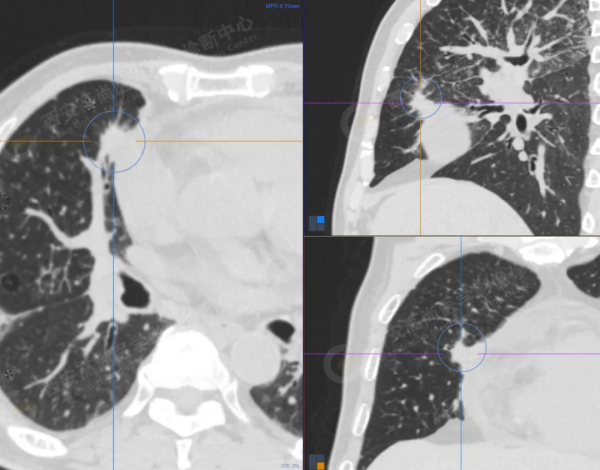

1.以下為肺內原發灶

1.右肺中葉內側段軟組織結節,呈淺分葉狀,邊緣可見毛刺及胸膜牽拉徵,呈FDG代謝異常增高,考慮為周圍型肺癌。